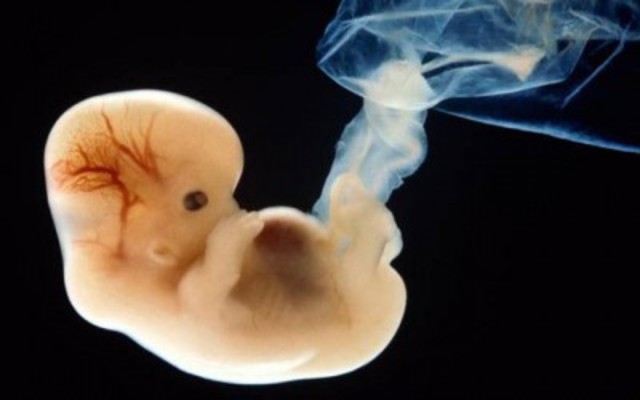

Semana 8

Los brazos y piernas se han alargado, sus manos y piernas comienzan a formarse y lucen como pequeños remos. El cerebro continua formándose; los pulmones ya empezaron a formarse. Ya hay una diferenciación sexual que fue determinada desde la fecundación.